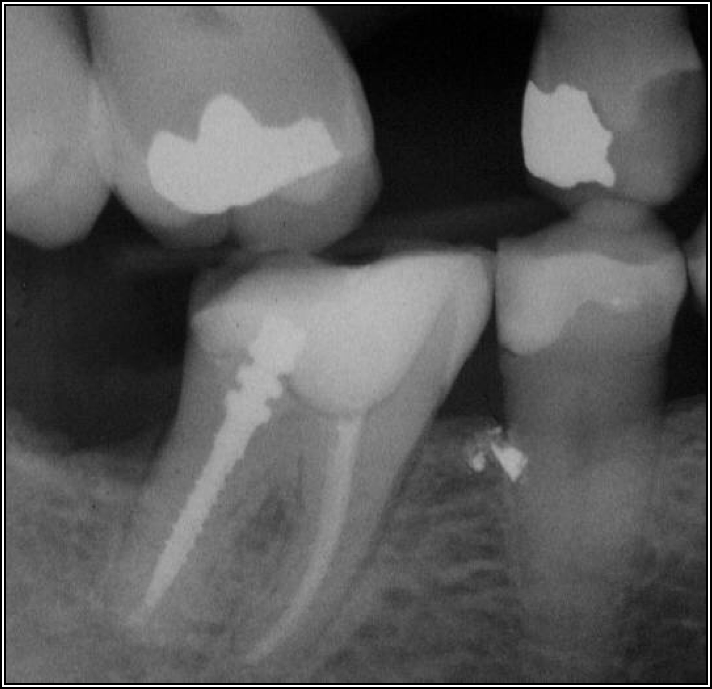

Occlusal Considerations

Occlusion is one of the most overlooked areas in endodontics; however, other than remaining structure, it is the most important factor.7 Patients who are heavy bruxers can cause the need for a root canal from the lateral forces. Patients who clench pose a different challenge with apical forces, yet the damage from both can be the same. Figure 7 shows a patient with bruxism. The patient had pain in response to hot and cold stimulus, and the clinicians needed a bitewing to determine which tooth was causing the pain. From the periapical (PA), it was clear that tooth No. 2 had a large problem, No. 3 had a crown, and No. 4 had a large restoration. Any of the three may have been the source of the problem.

With the bitewing shown in Figure 8, it became clear there was gross decay in tooth No. 3 that could not be seen on the PA, and there was a periodontal defect, a pulp stone, in No. 2. There was also a class V lesion revealing the bruxism, flat occlusion, multiple restorations in No. 30, a post in No. 31, and decay on No. 2 as well. The post in No. 31 was useless because when a post is placed, it must be the right length, width, and size. If the post is too short, there will be a greater fulcrum and the tooth will break. If it is too long, the clinician can break it by wedging it. If it is too short, it will not hurt the tooth, but it will not provide any valuable function. It is overall preferable to do posts in teeth having just single restorations rather than abutments for bridges because those teeth are already under greater force. If the technique is not performed correctly, iatrogenic issues may result.

Fig 7. Bruxism.

Figure 7

Fig 8. Bitewing revealed decay and other problems.

Figure 8